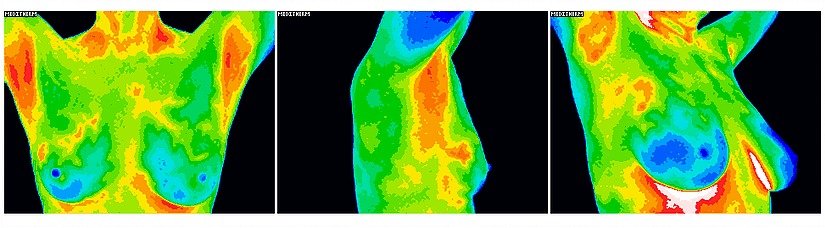

Thermography is a health screening procedure that uses a special infrared camera with highly accurate heat sensors to detect differentials in temperature in the body. By detecting these temperature changes, thermography can pinpoint abnormalities that are indicators of breast diseases, including cancer, Paget’s disease, and Fibrocystic breast disease.

Two baseline breast scans are conducted to establish a clear picture of your breast physiology, thereafter, annual scans are recommended to closely monitor your breast health.